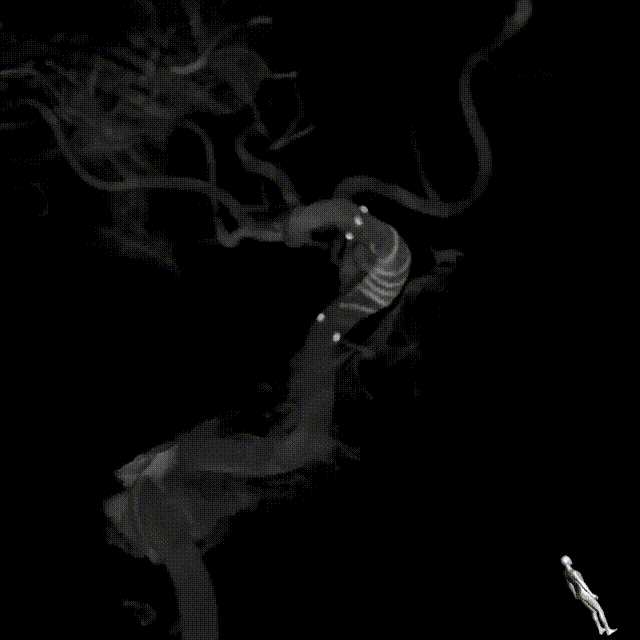

术中DSA造影:右侧颈内动脉3D造影提示:右侧颈内动脉床突旁大型动脉瘤,大小约为20.72×16.33mm,远端血管直径1.92mm,近端血管直径3.48mm。

完全释放FRED 4017血流导向密网支架辅助弹簧圈栓塞后,正、侧位及3D造影观察,载瘤动脉通畅、支架贴壁良好、动脉瘤内造影剂滞留。